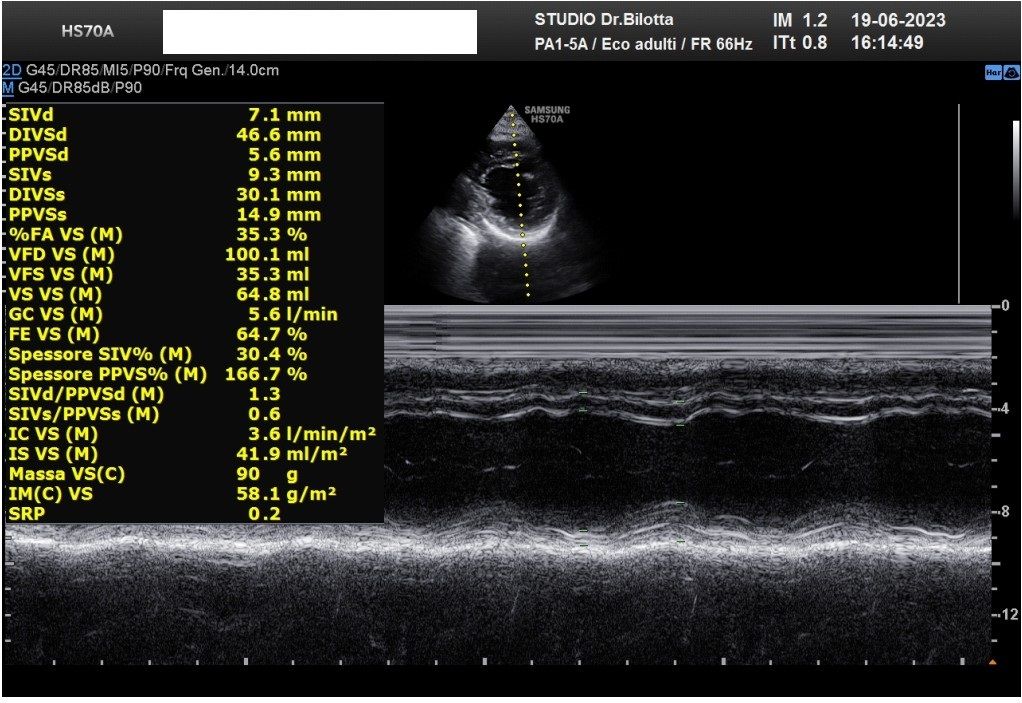

Diploma di maturità classica. Laurea in Medicina e Chirurgia con Lode a 26 anni. Specialista in Oncologia Generale Diagnostica e Preventiva con Lode a 31 anni. Specialista in Malattie Cardiovascolari a 36 anni. Medico generalista dal 1990 poi ospedaliero per trent'anni dal 1993 al 2022 nel corso dei quali ho refertato oltre 100 mila tracciati elettrocardiografici, effettuato oltre 30 mila consulenze specialistiche, praticato circa 10 mila esami ecocardiografici, condotto oltre 2 mila test ergometrici sia su cicloergometro che su treadmill, visionato circa 1500 esami Holter Ecg e ABP ( Ambulatory Blood Pressure ) occupandomi prevalentemente di prevenzione cardiovascolare, ipertensione arteriosa, cardiopatia ischemica, valvulopatie. Dal 2023 ho deciso di trasferire le mie competenze nella libera professione presso il mio studio privato che è stato allestito in linea alle moderne esigenze tecnologiche. Metodiche diagnostiche attualmente praticate: Elettrocardiografia a riposo, Ecocardiografia mono-bidimensionale, PW, CW, Colordoppler tridimensionale, GLS Strain Speckle tracking, Monitoraggio Holter Pressorio delle 24 ore, Monitoraggio Holter ECG 12 canali dinamico delle 24 ore.

Foto e video